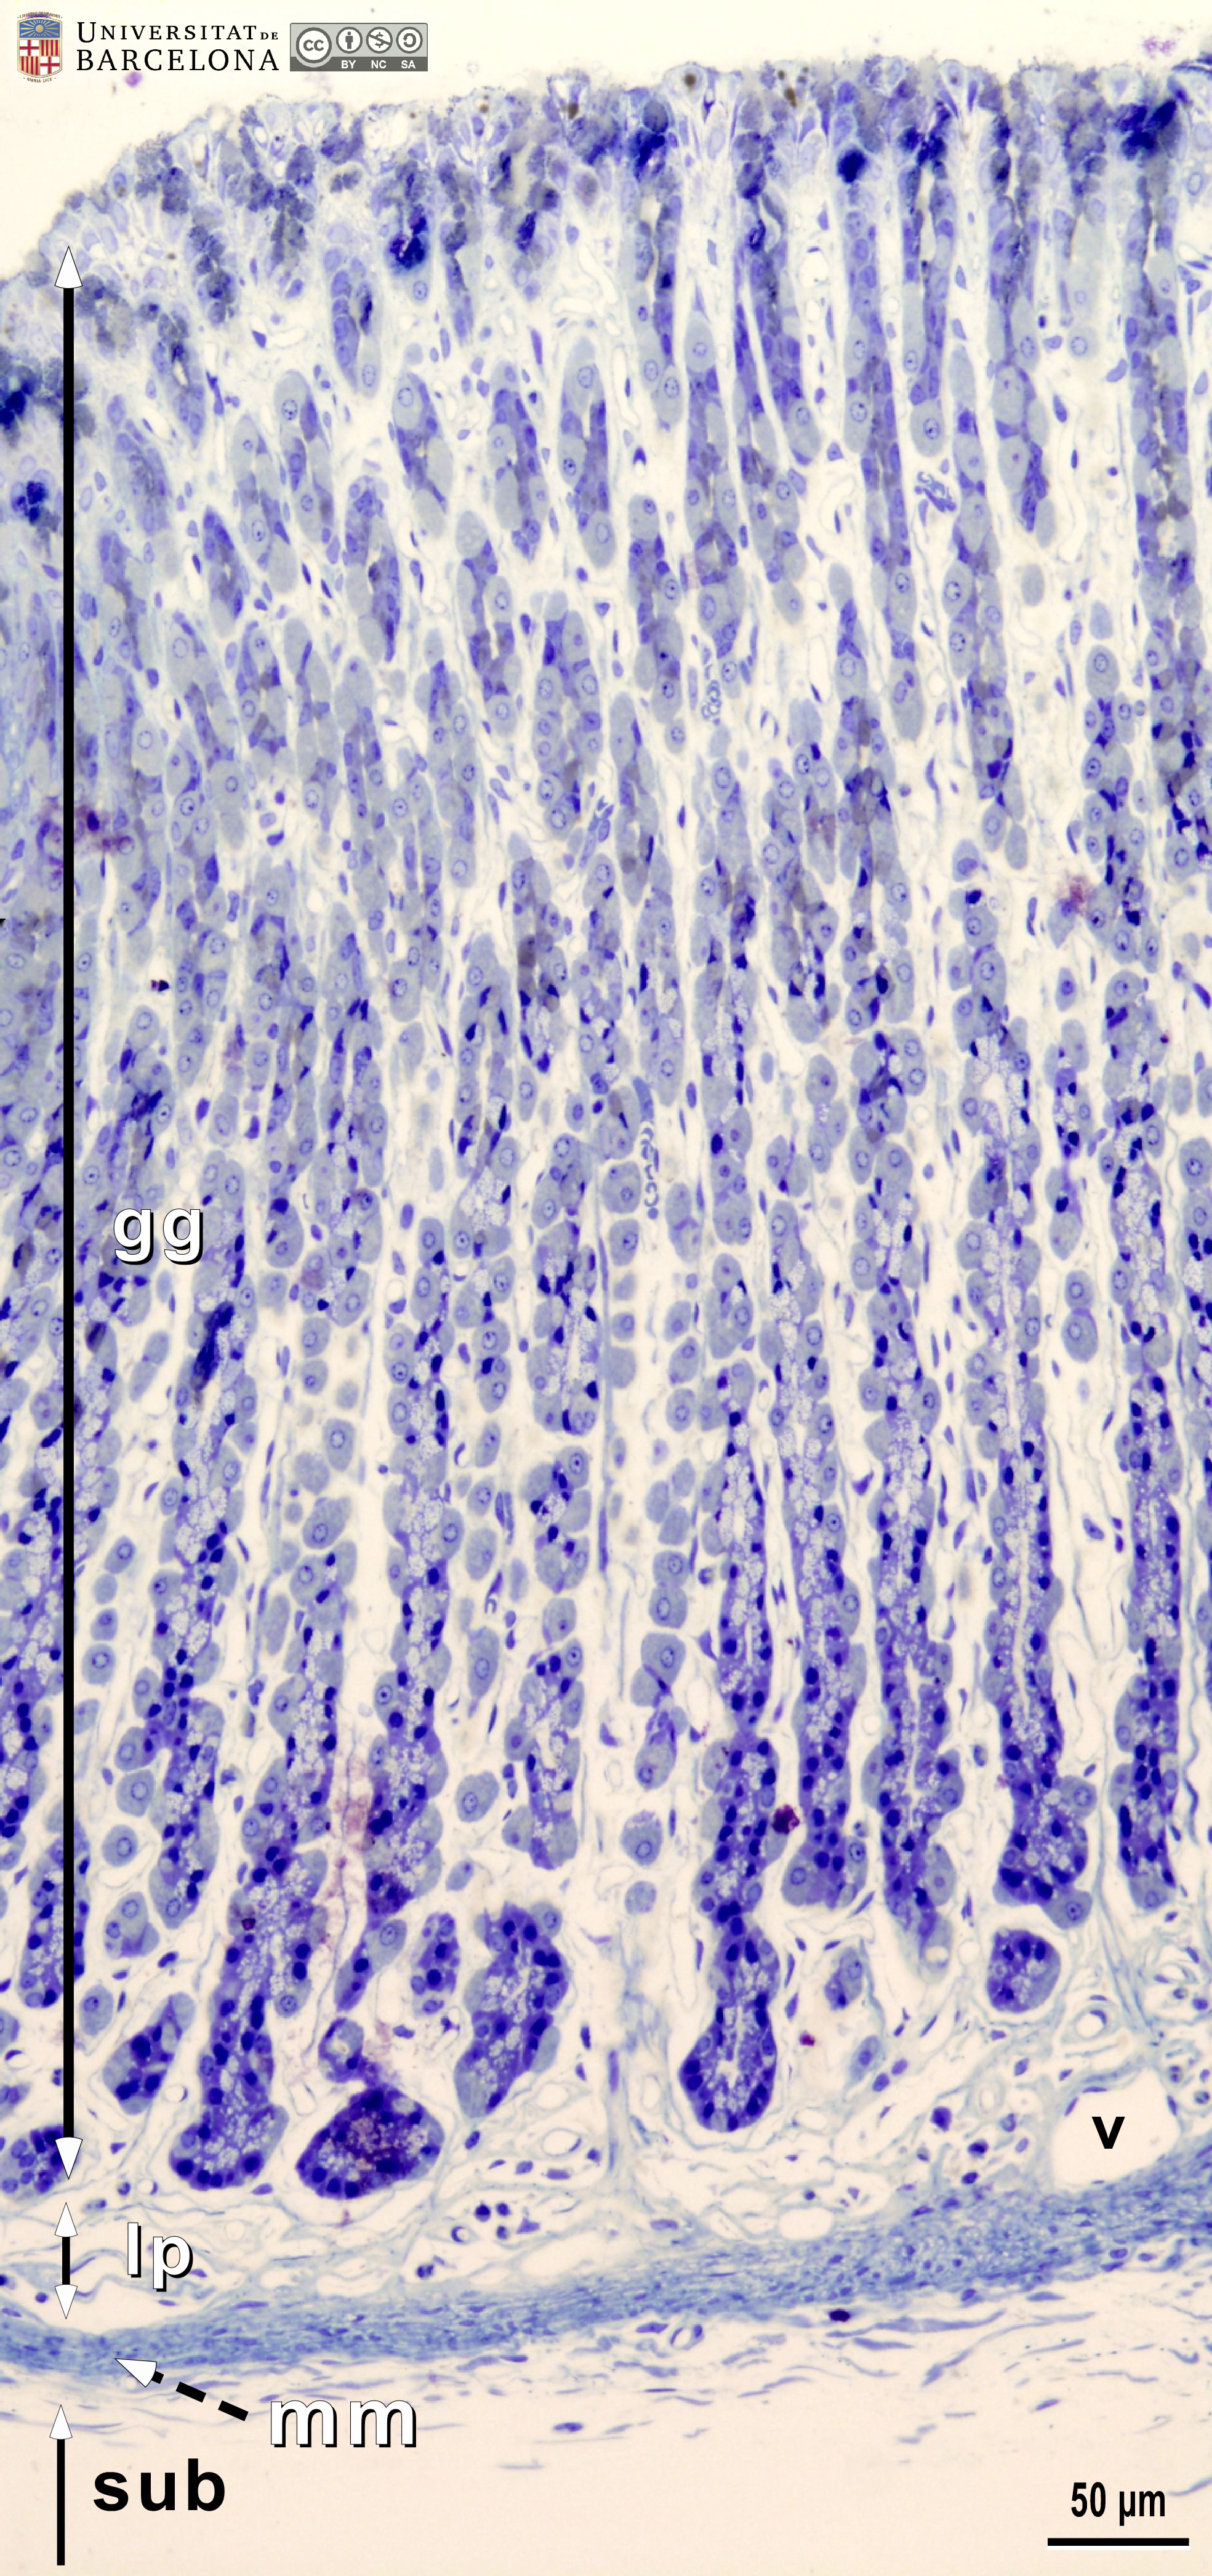

[ENG] A collection of micrographs illustrating the organisation of the stomach in rats. The layers of the gastric wall and their components –such as blood vessels, fibres and cell types– are shown in paraffin sections stained with hæmatoxylin-eosin stain or van Gieson trichrome. Semithin sections 2 µm thick were stained with toluidine blue. This collection complements the micrographs published by Dr Elena Sagristà i Mateo https://hdl.handle.net/2445/60213 — See also: https://diposit.ub.edu/dspace/browse?type=author&value=Sagrist%C3%A0+i+Mateo%2C+Elena

[CAT] Col·lecció de micrografies de l'organització de l'estómac de la rata. Es mostren les capes de la paret estomacal i els seus components (vasos sanguinis, fibres, tipus cel·lulars, etc.) en talls de parafina tenyits amb hematoxilina-eosina o el tricròmic de van Gieson i talls semifins de resina epoxi tenyits amb blau de toluïdina. Aquesta col·lecció complementa les micrografies publicades per la Dra. Elena Sagristà i Mateo https://hdl.handle.net/2445/60213 — I també: https://diposit.ub.edu/dspace/browse?type=author&value=Sagrist%C3%A0+i+Mateo%2C+Elena